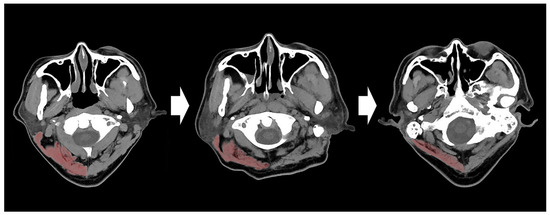

2. Materials and Methods

3.2. Relationship between C1-CSAs, TMTs, and Neurological Outcomes